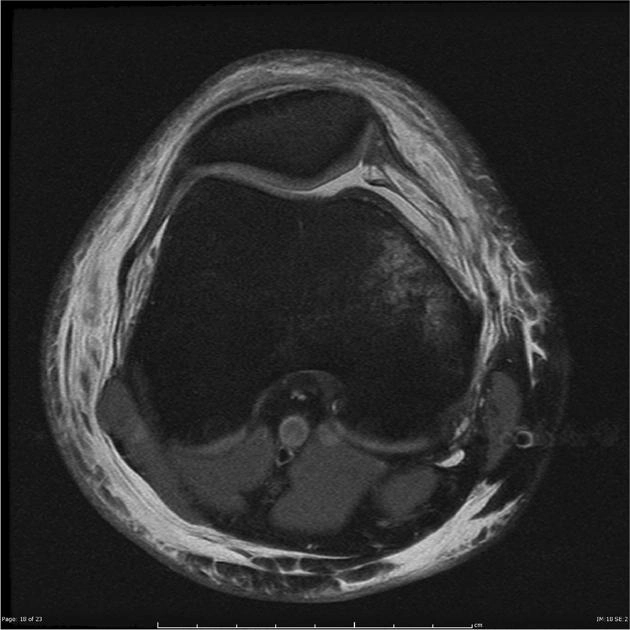

Rách dây chằng chéo trước ACL (Anterior cruciate ligament tear)

Rách dây chằng chéo trước (ACL) mạn tính

Thoái hóa nhầy của dây chằng chéo trước (Anterior cruciate ligament (ACL) mucoid degeneration)

Bộ ba bất hạnh của O'Donoghue (O'Donoghue unhappy triad)